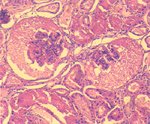

1. 膀胱: 黏膜上皮局部脫落,黏膜層及黏膜下層局部廣泛性出血。 2. 尿道: 黏膜移形上皮脫落,固有層呈淡粉紅均質樣壞死,大量RBC及少量淋巴球浸潤。 3. 腎臟: 多數腎小管上皮細胞發生廣泛性變性、壞死,管腔內有粉紅色滲出物。少數鮑氏囊空隙增大,內含淡粉紅色滲出液。髓質部則出血。 四、 微生物學檢查: 膀胱以血液培養基之培養,經鑑定為 Staphylococcus spp.。 五、 診斷: 山羊尿道結石併發膀胱破裂(Urolithiasis in Goat with Perforation of Urinary Bladder)。